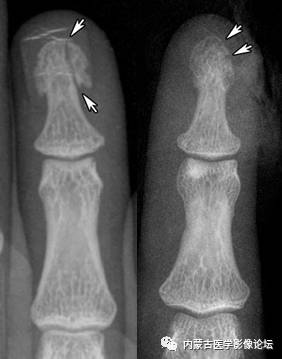

正常指骨粗隆:环指远节指骨粗隆呈不规则分叶状(白箭),部分呈透亮线改变(箭头),但边缘清晰,轮廓线连续,不应误为骨折线或病理改变。

指骨粗隆骨折:指骨粗隆骨皮质不连续(白箭),呈透亮线影